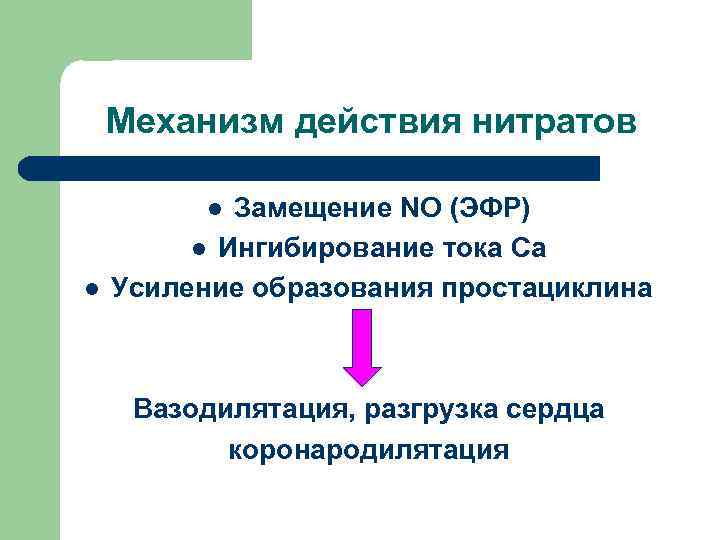

Механизм действия нитратов Замещение NO (ЭФР) l Ингибирование тока Ca Усиление образования простациклина l l Вазодилятация, разгрузка сердца коронародилятация